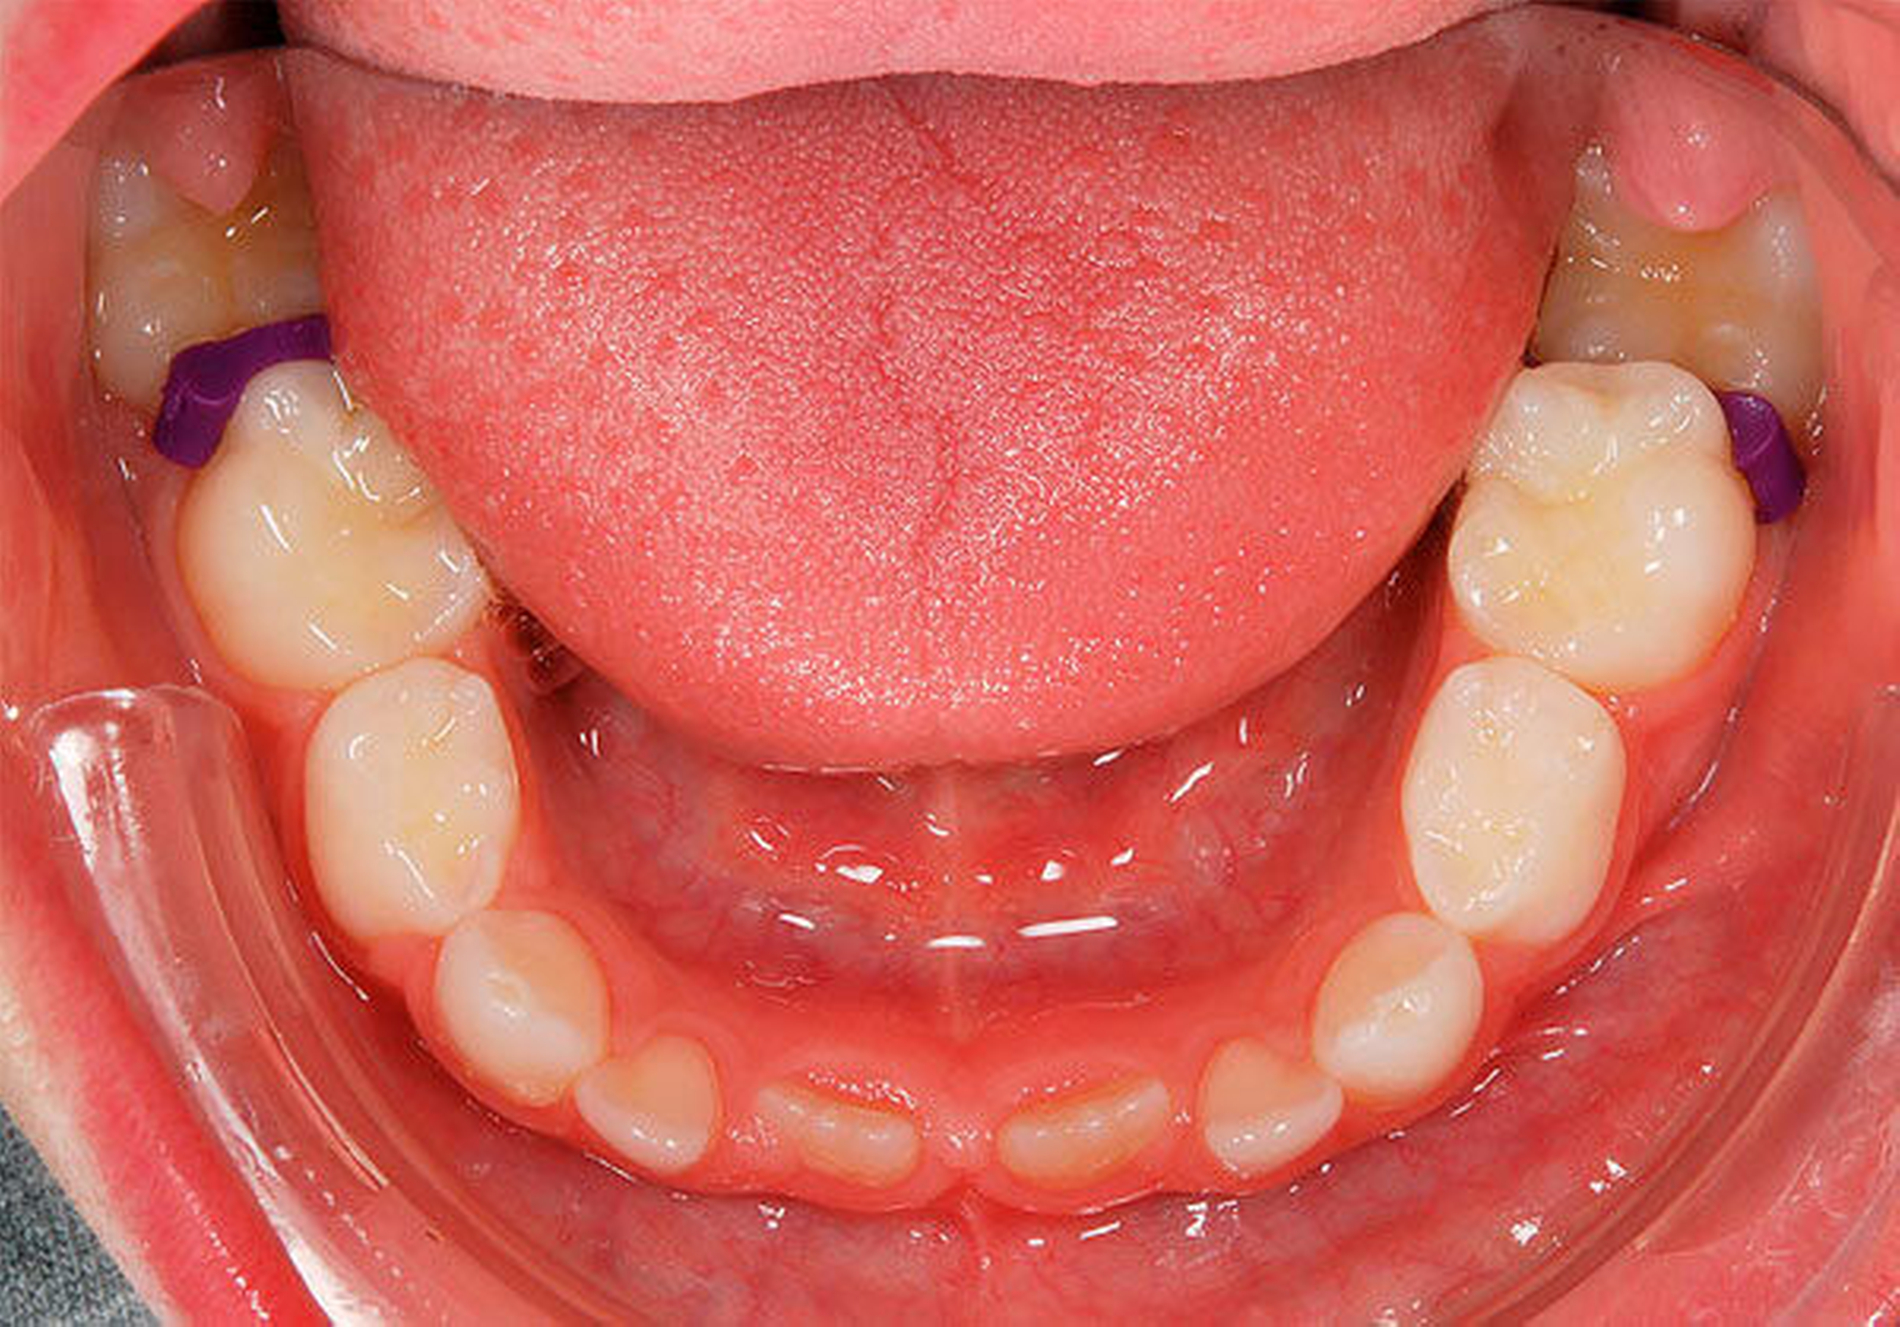

Ausgeprägte Zahnfehlstellungen und Gebissanomalien zeigen sich im reinen Milchgebiss deutlich seltener als im Wechsel- oder im permanenten Gebiss [Schopf, 2003]. Dennoch sollten bereits in dieser frühen Phase beispielsweise die Platzverhältnisse für die später durchbrechenden Zähne beurteilt werden. Im Säuglingskiefer liegen die Zahnkeime der Milch-Inzisiven zunächst in einer sagittalen Staffelstellung [van der Linden, 1980]. Die mit dem Durchbruch der Milchzähne einhergehende Bildung des Alveolarfortsatzes und die wachstumsbedingte Vergrößerung der Zahnbögen führt meist zu einer lückigen Stellung der Milchschneidezähne [Sillman, 1964] (Abbildung 1). Diese Lücken tragen dazu bei, den deutlich breiteren bleibenden Nachfolgern eine regelrechte Einordnung in den Zahnbogen zu ermöglichen [Moyers, 1976; Leighton, 1978]. Ein „schönes“, lückenloses Milchgebiss oder gar Engstände in der Front sind ein Alarmsignal im Hinblick auf spätere Platzprobleme für die bleibenden Zähne [Leighton, 1969]. Bei diesen Patienten ist eine intensive Überwachung während des Zahnwechsels der permanenten Inzisiven ratsam, um gegebenenfalls rechtzeitig Platz schaffende Maßnahmen einleiten zu können.